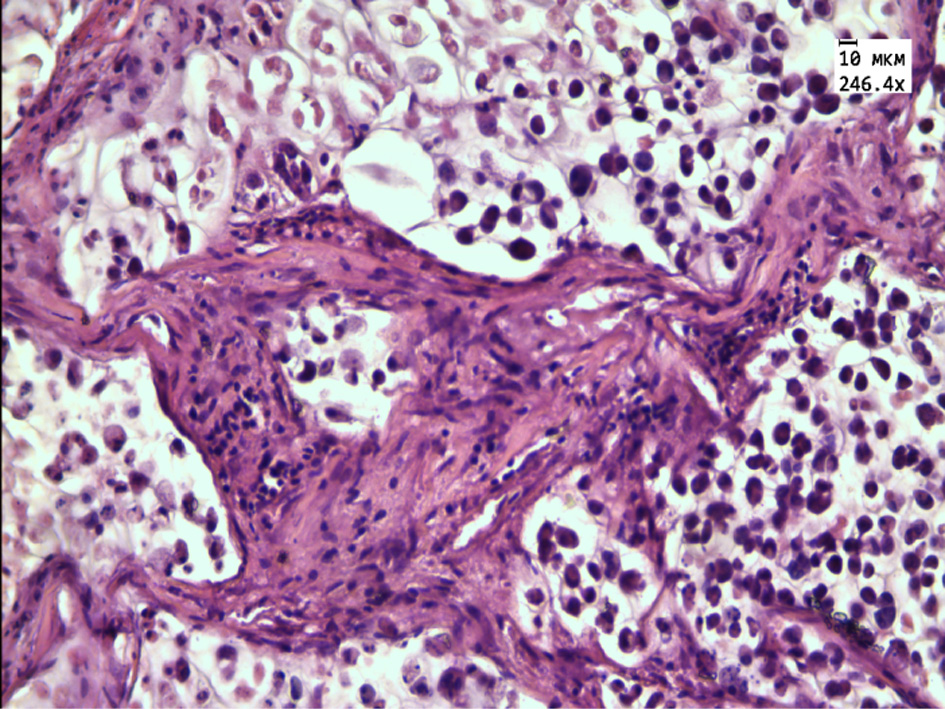

In the group of rats receiving aqueous extract of thyme, the tumor is represented by small rounded cells with a reduced flattened nucleus located on the periphery of the tumor tissue. The central parts are represented by extensive necrotic foci, a large number of “shadow cells” and thickened connective tissue partitions with a large number of blood vessels, as well as extensive clusters of tumor cells with signs of karyopycnosis, nuclear chromatin condensation and karyorexis, and a large number of apoptotic cells (Fig. 3, 4).

Figure 4 – Histological structure of transplanted hepatic cancer in the group receiving aqueous extract of Thymus marschallianus Willd.

Note: nuclear chromatin condensation and karyorexis in tumor cells (white arrow). Stained with hematoxylin and eosin. Magnification 246.4×